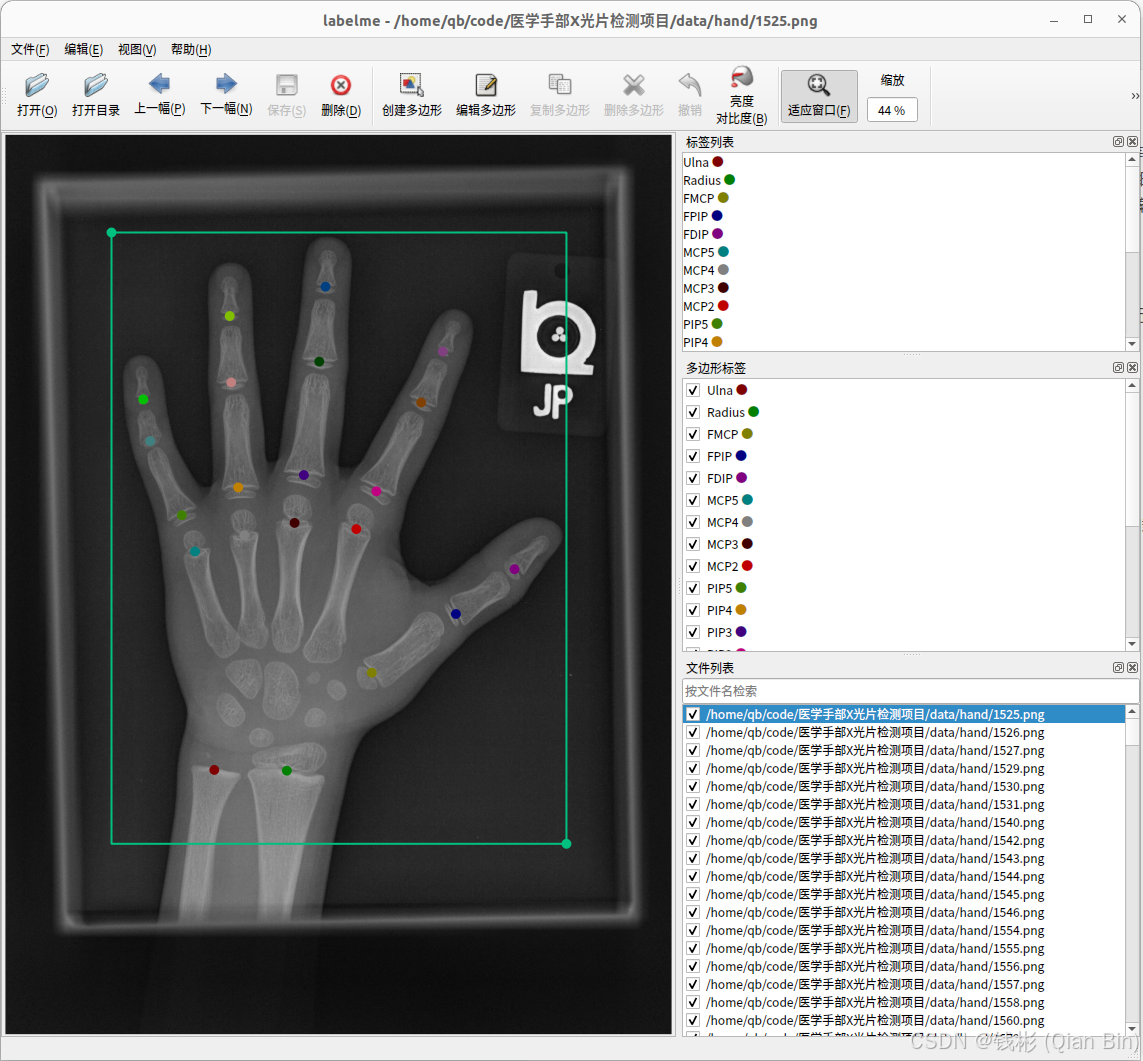

单击工具栏上的打开目录按钮,找到data/hand_labelme文件夹并打开。打开后会自动加载该目录下的所有X光图片,并且自动叠加了标注信息在上面。如下图所示:

整个标注信息包括两部分:手部矩形框、手部关键点。其中手部矩形框在本项目中只有1个类别,而关键点在本项目中有21个。

该数据集中每张png图片都对应一个标注好的同名的json标注文件,存放在同一目录中。

如果想要自行标注也可以,标注方法如下:

(1)先标注关键点:选择“编辑”->"创建控制点",然后依次开始标注关键点。在给关键点命名时不能出现中文或特殊符号;

(2)再标注矩形框:选择“编辑”->"创建矩形",然后开始标注目标矩形框。同样,在给矩形框命名时不能出现中文或特殊符号。

在整个标注过程中尤其要注意,每个关键点都需要严格包含在对应目标的矩形框内,不能有某个关键点同时出现在多个矩形框内的情况。